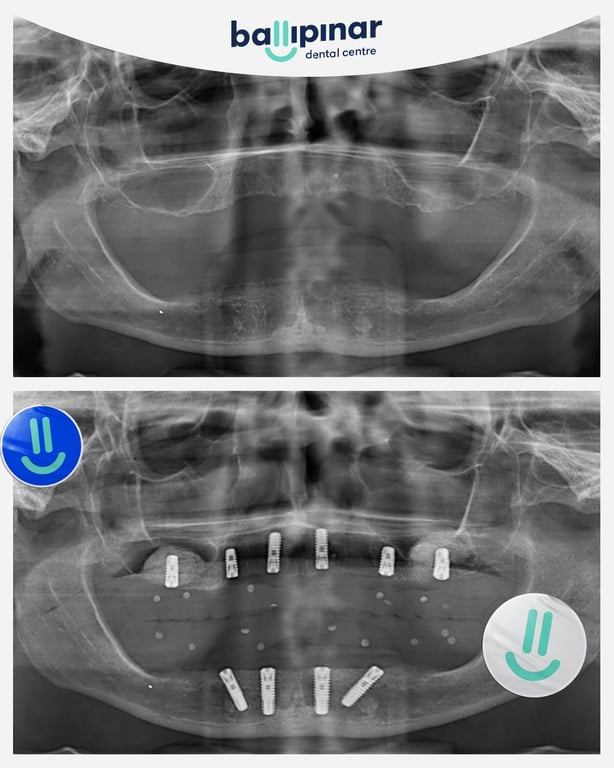

Dental implants Before & After

Explore all the before and after photos of dental implant procedures performed by Ballipinar in Turkey. Contact us today to achieve a beautiful smile.